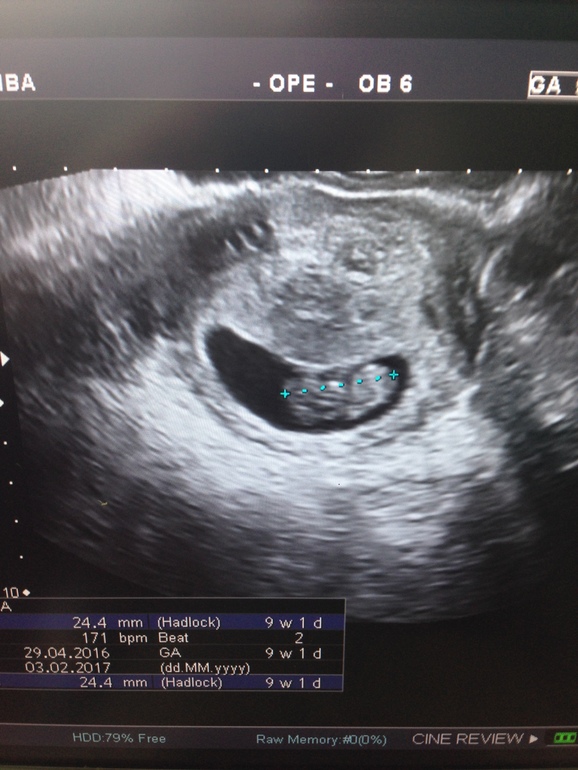

Ребенок не может занять правильную позицию ! КТР на 12 неделе